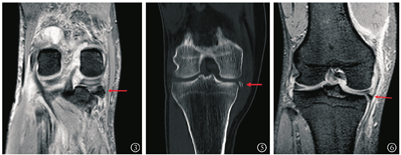

病例1 患者男,52岁,因"机器压伤致左大腿、右膝疼痛活动受限12 h"于2018年1月入院。入院查体:左侧大腿肿胀压痛,畸形,右膝关节肿胀压痛,活动受限,双下肢肢端血供感觉正常,由于疼痛查体欠配合。入院完善左侧股骨正侧位X线、右膝X线(图1)、CT(图2)及MRI(图3),诊断"左侧股骨干骨折、右侧反式Segond骨折"。为控制创伤,行分期手术。入院7 d后患者一期行"左侧股骨干骨折切复内固定术",术后恢复可。入院14 d行右膝关节镜辅助下内固定手术。麻醉下查体提示右膝关节30°外翻试验阳性,前后抽屉及Lachman试验阴性,术中常规行关节内血肿清理后发现前后交叉韧带无损伤,内侧半月板(medial meniscus,MM)撕裂予半月板成形,内侧撕脱骨折位于内侧半月板后角下方并向内侧移位,关节镜监视下克氏针体外定位骨折位置后取膝关节内侧2 cm切口纵行劈开内侧副韧带分离至骨折处,见骨折块约1.5 cm×1 cm×1 cm大小并翻转,在关节镜监视下复位骨折后用2枚3 mm空心钉固定,再可吸收线连续缝合修补内侧副韧带(medial collateral ligament,MCL),术后复查右膝X线(图4)示骨折解剖复位。术后常规佩戴可调节膝关节支具伸直位固定并行直腿抬高锻炼股四头肌,术后4周开始膝关节0°~90°屈曲活动,术后6周膝关节0°~120°屈曲活动并拄双拐保护下开始部分负重,术后10周膝关节完全负重并达到正常活动度。目前术后半年,查外翻试验转阴,日常生活无不适,能慢跑,打羽毛球,右膝无不稳感,Lysholm评分90分。

病例2 患者男,50岁,因"摔伤致右膝关节疼痛3 d"于2019年2月入院。入院查体:右膝关节肿胀压痛,活动受限,肢端血供感觉正常。入院查右膝CT(图5)及MRI(图6)提示右膝后交叉韧带止点无移位骨折,胫骨平台内后缘撕脱骨折累及内侧副韧带深层,诊断"反式Segond骨折"。完善术前准备后行右膝关节镜手术,麻醉下查体示右膝关节肿胀,前后抽屉及Lachman试验阴性,内外翻试验阴性。术中清理血肿后探查前后交叉韧带完整,后叉止点骨折无移位,发现内侧半月板后角撕裂行内侧半月板成形,内侧撕脱骨折块位于内侧半月板下方并翻转,细针定位骨折块位置后取膝关节内侧3 cm切口,分离至骨折部位,见骨折块菲薄约1 cm×0.5 cm×0.3 cm,连及内侧副韧带深层,考虑骨块太小空心钉固定困难改用缝线捆扎,复位后在关节镜监视下在骨折块前外及后外建立2 mm骨隧道,用硬膜外导针过线,将2号爱惜绑线捆扎复位骨折块,平台内侧放置小T型钢板作为阻挡支撑,将爱惜绑线打结在钢板上,术中关节镜探查骨折解剖复位(图7,图8,图9,图10)。术后复查CT进一步证实示骨折解剖复位(图11)。术后常规佩戴可调节膝关节支具伸直位固定并行直腿抬高锻炼股四头肌,术后2周开始膝关节0°~90°屈曲活动,术后6周膝关节0°~120°屈曲活动并拄双拐保护下开始部分负重,术后10周膝关节完全负重并达到正常活动度。术后半年复查,患者右膝无疼痛,能慢跑,Lysholm评分95分。